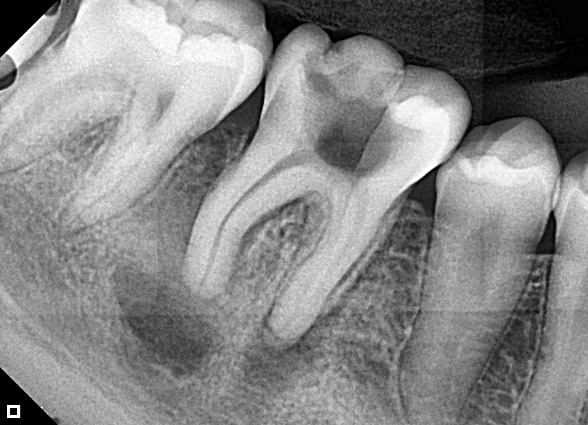

1-Year Follow-Up showing the complete healing of the periapical lesion on teeth #11 and #12